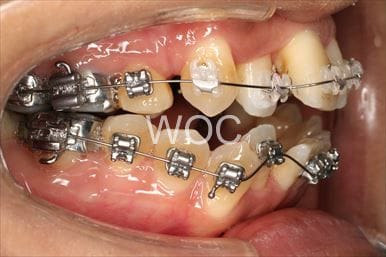

出っ歯上のみ舌側矯正、下はエッジワイズ装置

上は舌側矯正で希望。第一選択は上顎両側第一小臼歯の抜歯だったが、ボーダーラインケースであり改善なければ抜歯することを了承のうえ、非抜歯治療で開始。非抜歯で終了しました。

- 年齢:28歳女性

- 主訴:出っ歯、前歯が曲がっているのが気になる

- 基本矯正料金:103万円

- 治療期間:1年8ヶ月

- 非抜歯